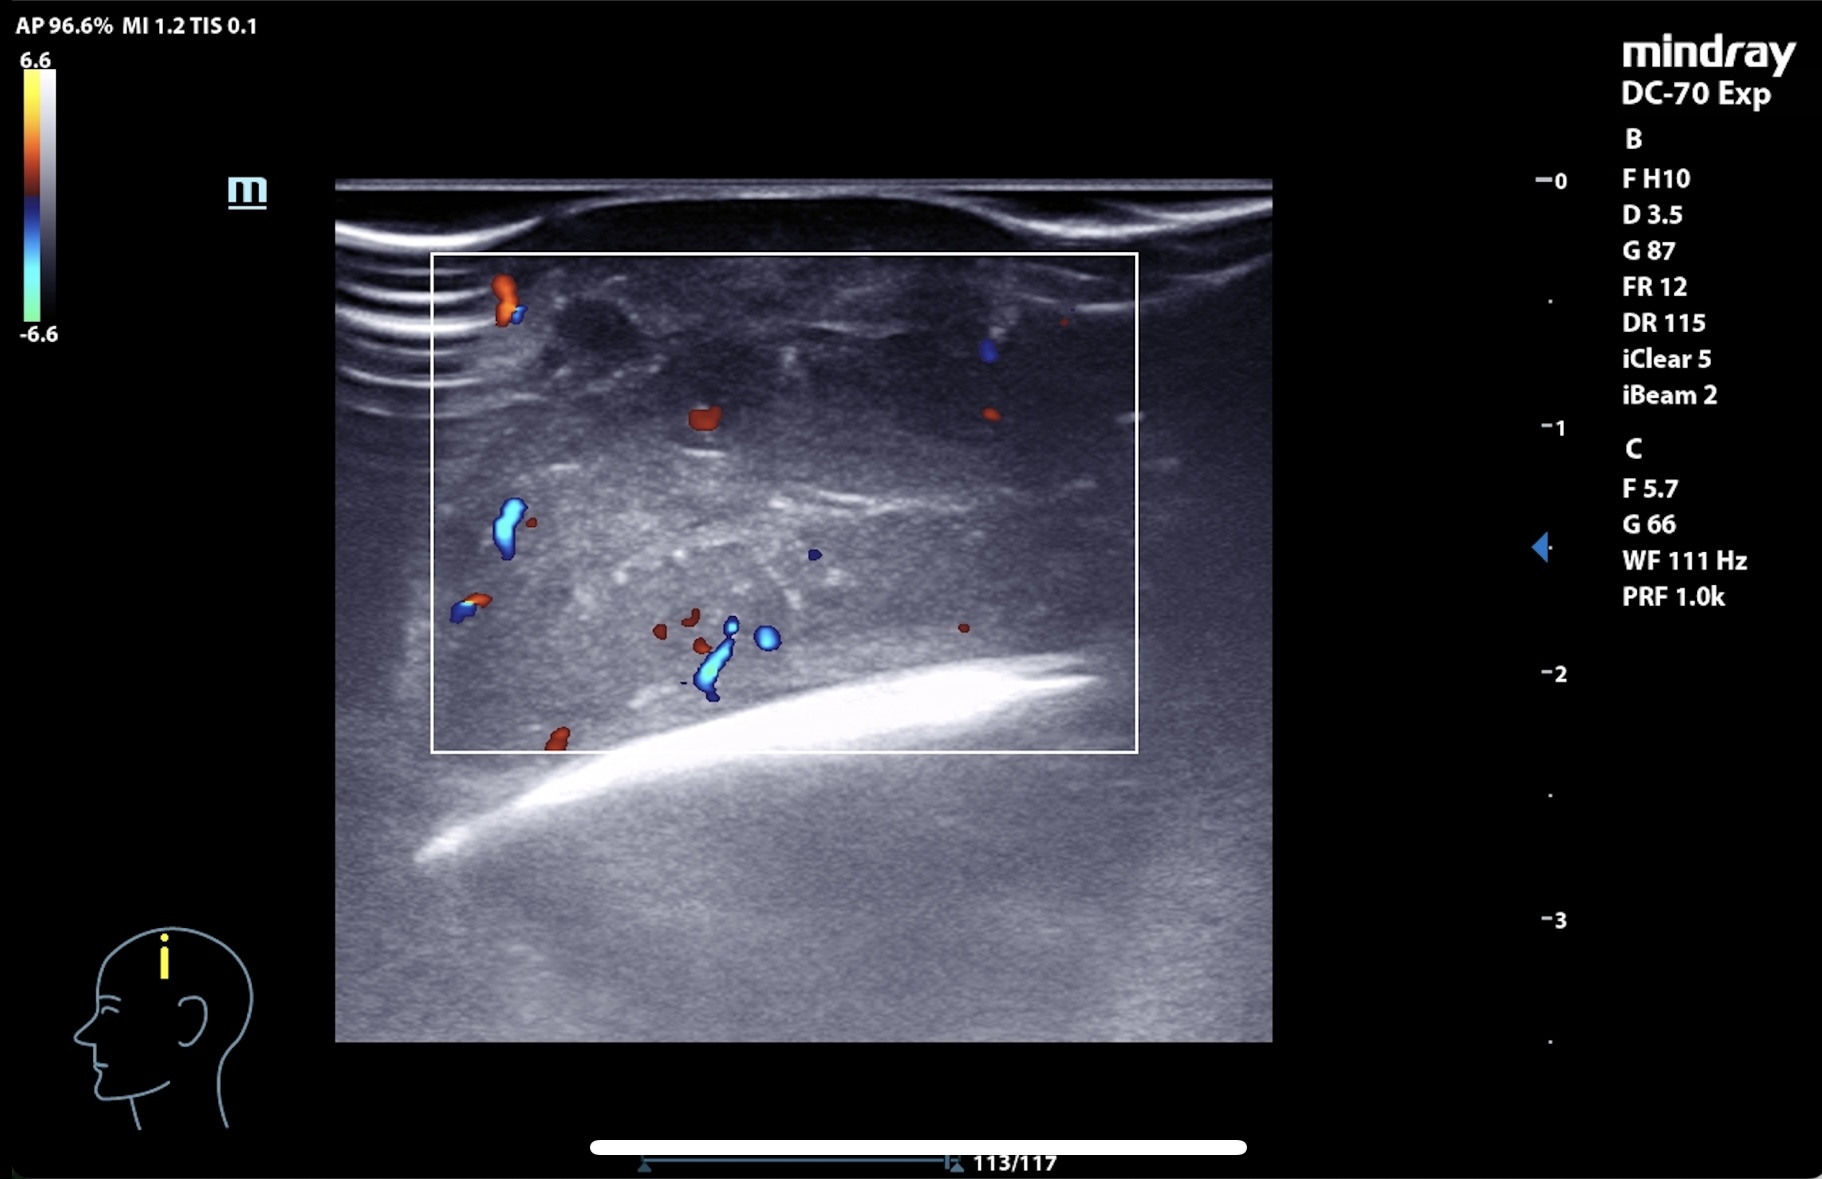

Se realiza en consulta ecografía, donde, para evitar la contaminación, se utiliza una funda estéril con gel conductor en su interior y clorhexidina entre la sonda y el cuero cabelludo como conductor líquido.

La imagen muestra una lesión heterogénea, con bordes netos, pero sin cápsula, microcalcificaciones en su interior y zonas hipoanecogénicas de necrosis líquida interna, así como vascularización interna intensa en Doppler. El patrón sugería proceso infiltrativo, por lo que se priorizó derivación urgente a dermatología.